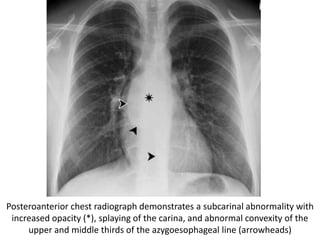

Posteroanterior chest radiograph demonstrates a subcarinal abnormality with

increased opacity (*), splaying of the carina, and abnormal convexity of the

upper and middle thirds of the azygoesophageal line (arrowheads)

Corresponding CT scan helps confirm a subcarinal mass

(arrow), which proved to be a bronchogenic cyst.